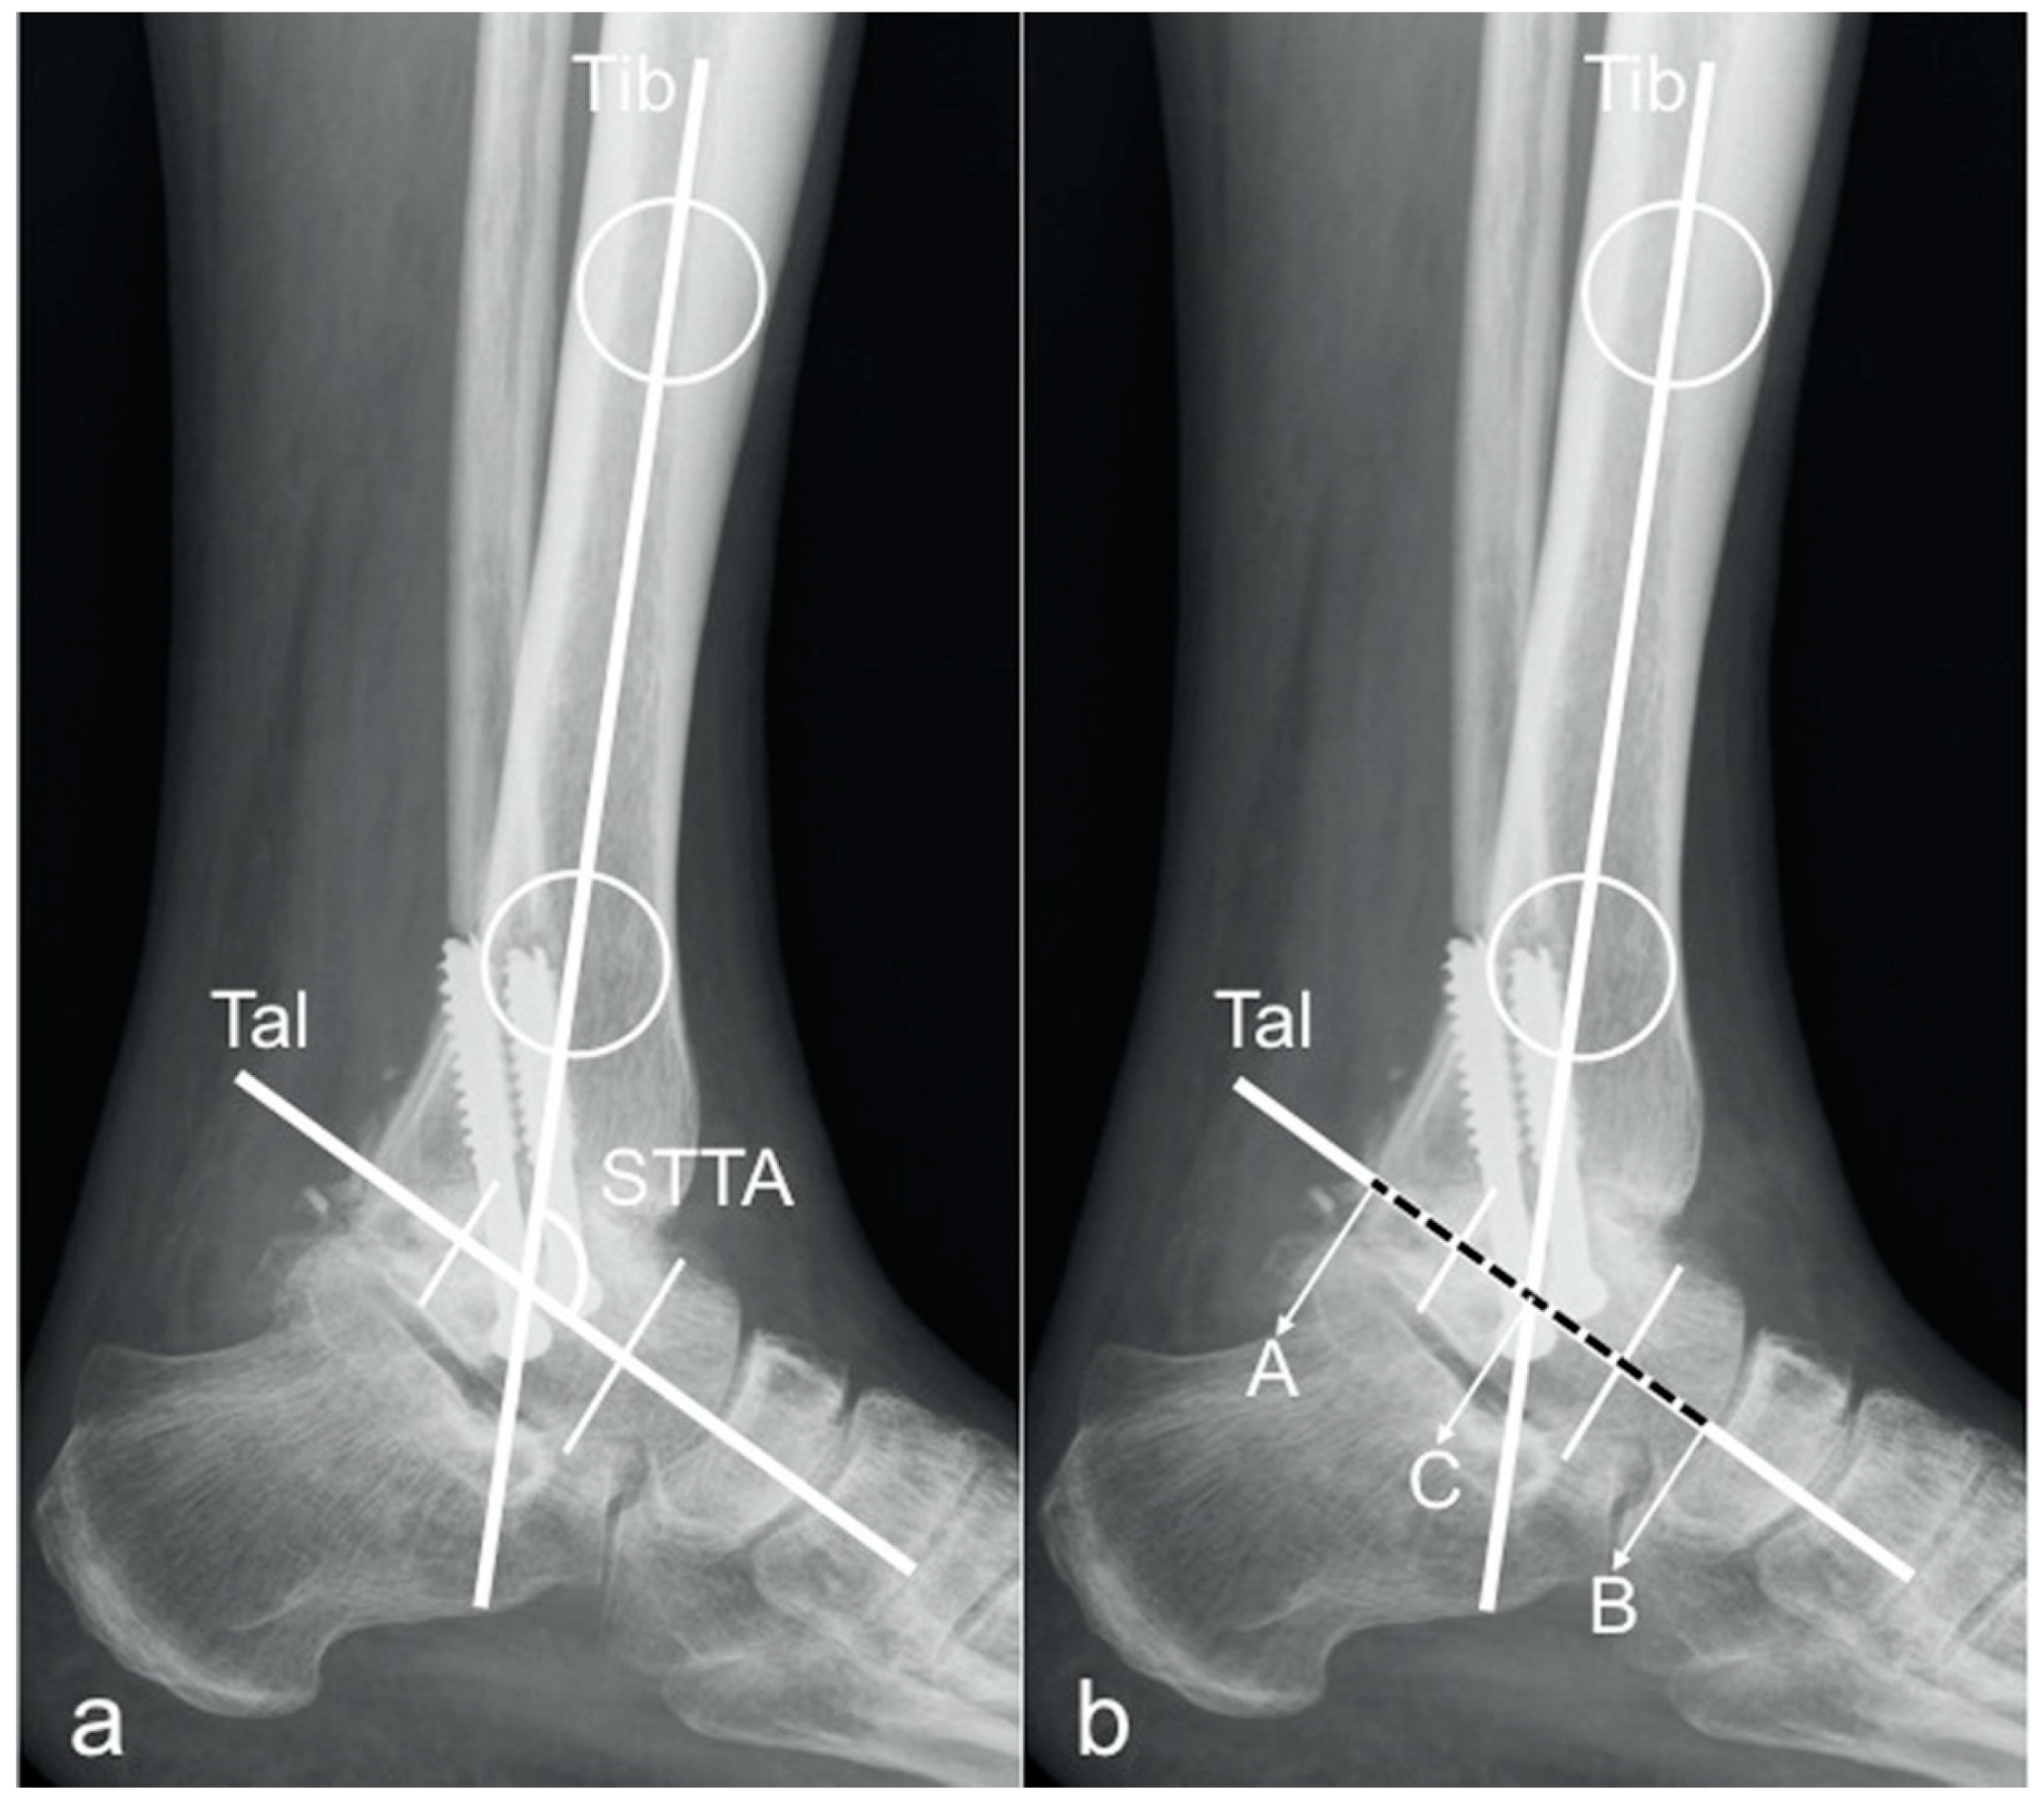

2.1. Radiographic Measurements

- tibCOR:

- procLAT:

- the distance from the tip of the lateral process of the talus to the longitudinal axis of the tibia [9].